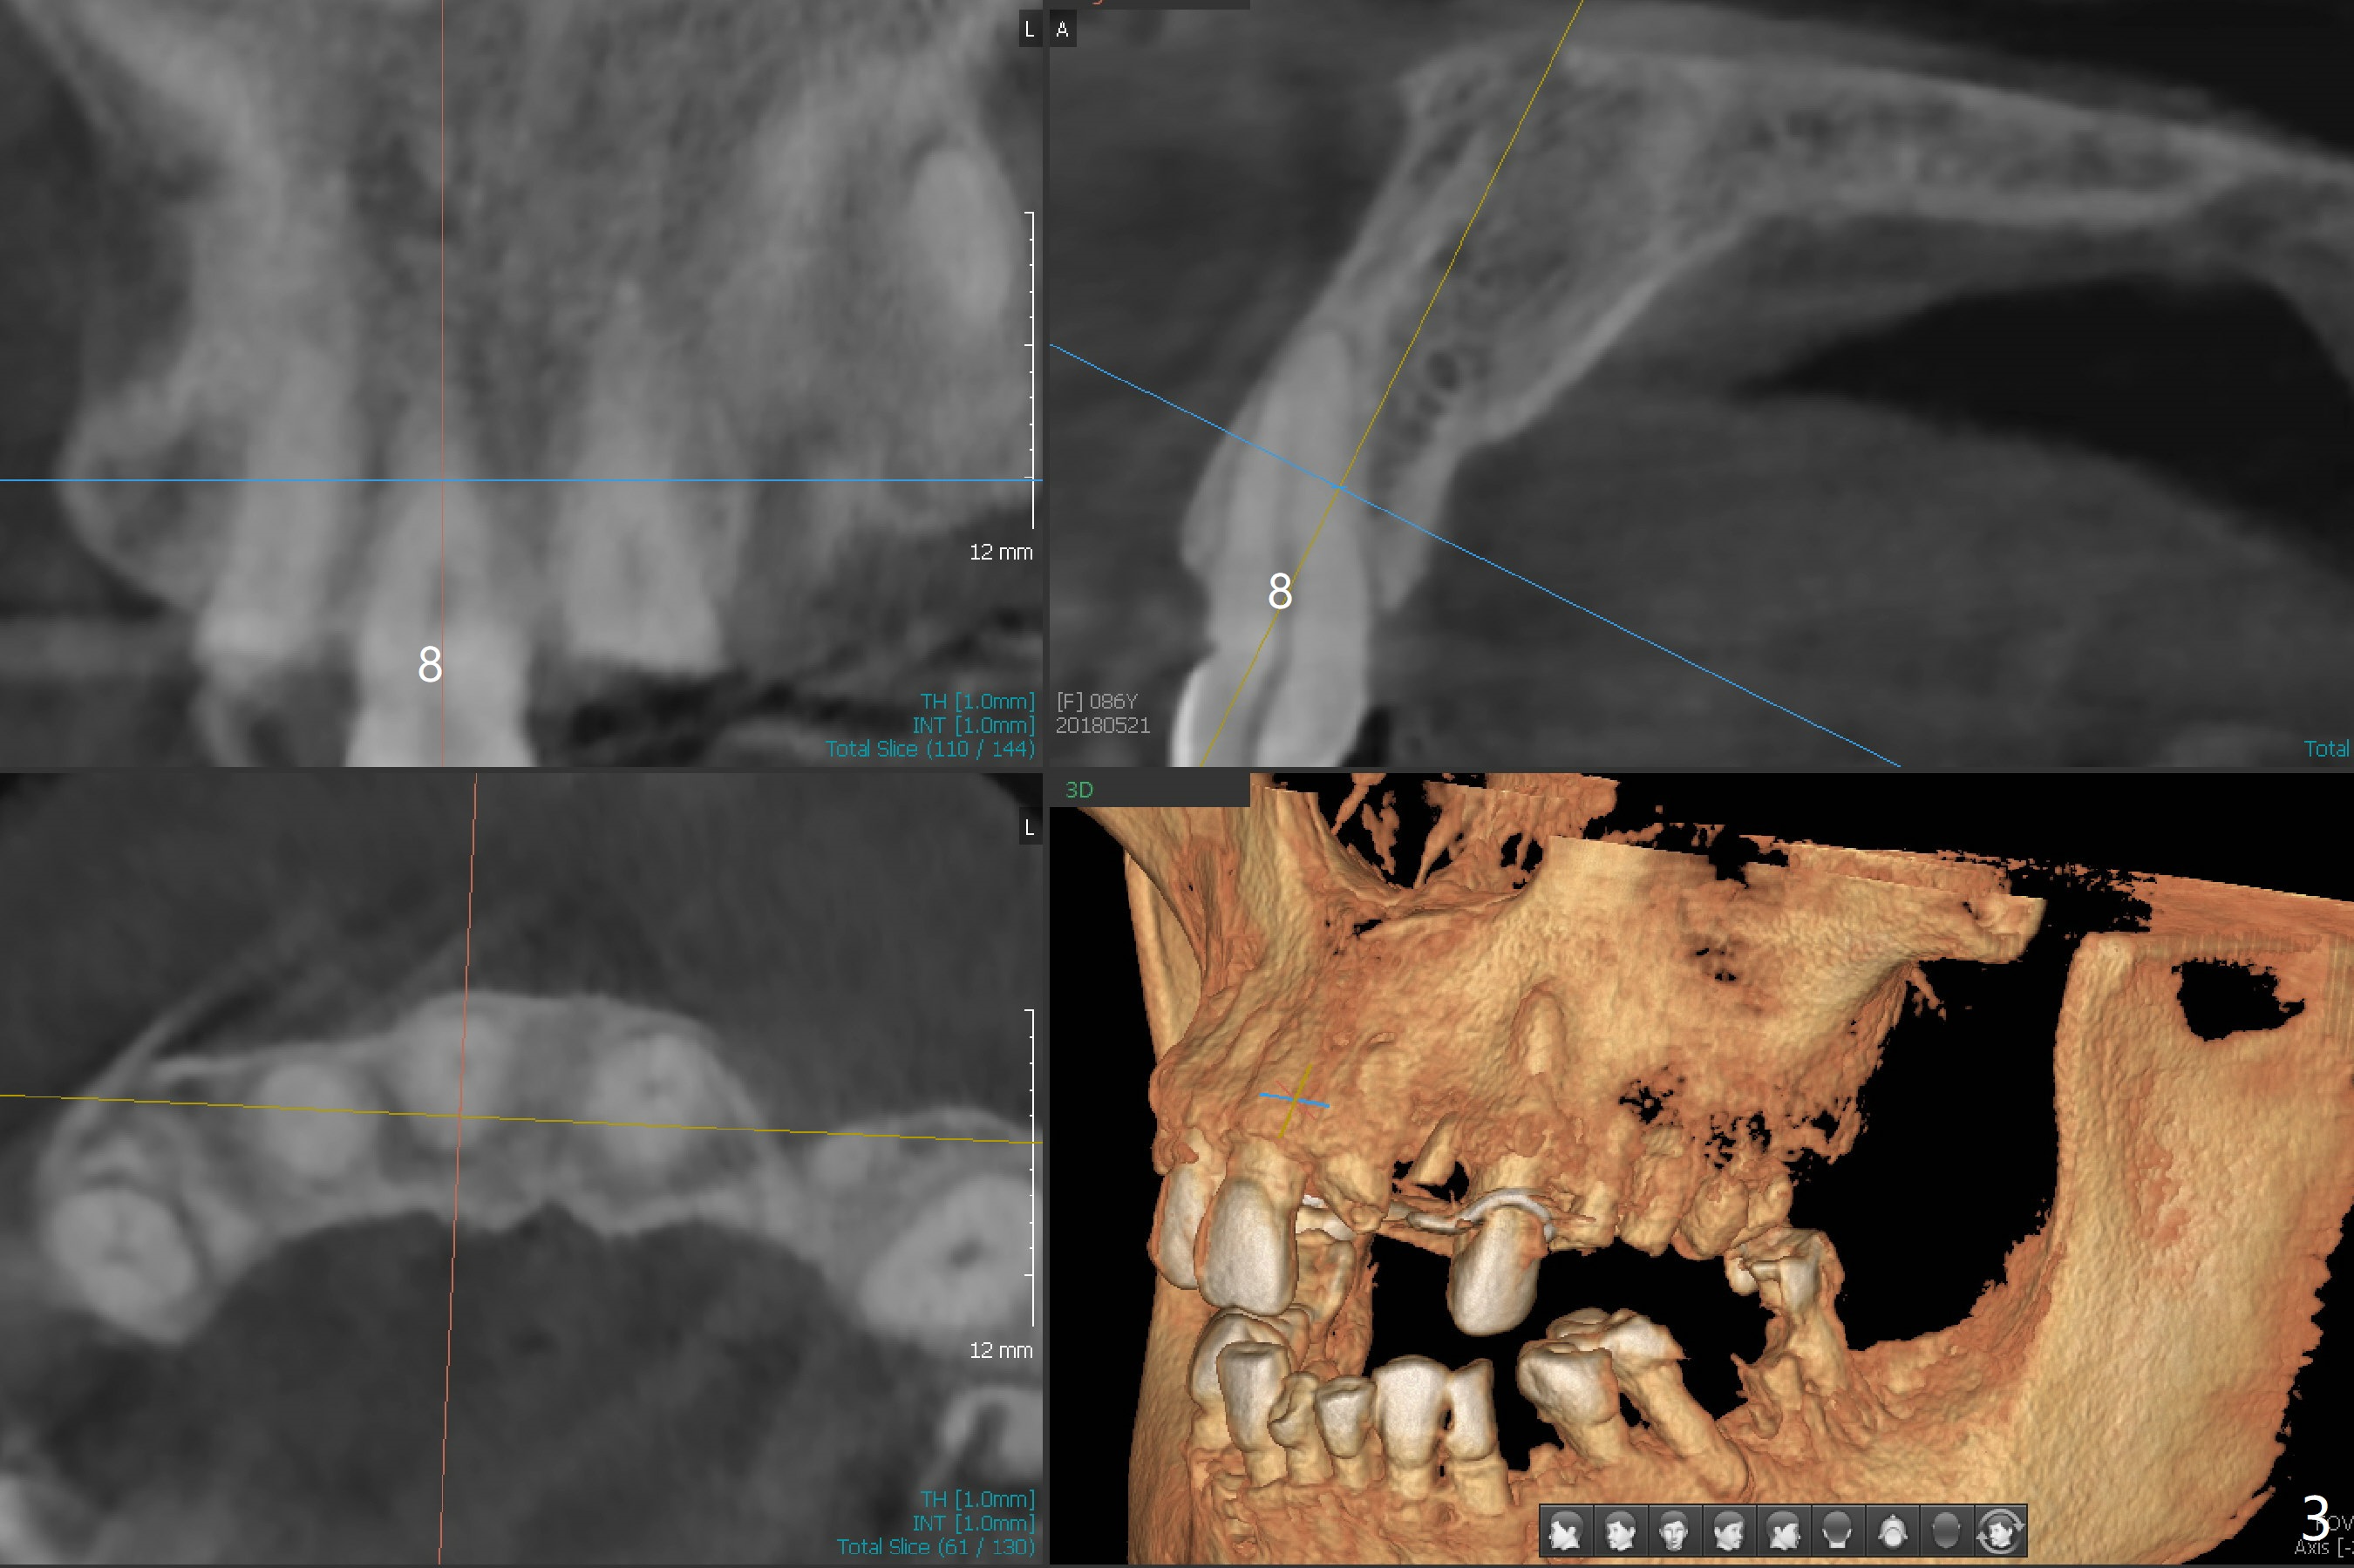

A 86-year-old woman with diabetes (under control with Insulin) and poor dentition (Fig.1) presented to clinic with an abscess apical to the tooth #8 (nonvital, Fig.2). CBCT (Fig.3) or PA (Fig.4) does not show radiolucency at #7 or 8. The incised abscess with purulent drained is superficial to the apparently intact periosteum (Fig.5 *). The patient is reluctant to have #7 and 8 extracted, since they are the only remaining functional dentition. The infection recurs 1.5 months later (Fig.6 * (^: previous incision)). With the periosteum elevated, fenetration over the apex of the tooth #7 (vital in pulpal test) is only seemingly significant finding (Fig.7). The abscess (Fig.8 A) is shown superficial to the periosteum (*). The infection is expected to relapse. What should be done otherwise? Full mouth extraction has been discussed.